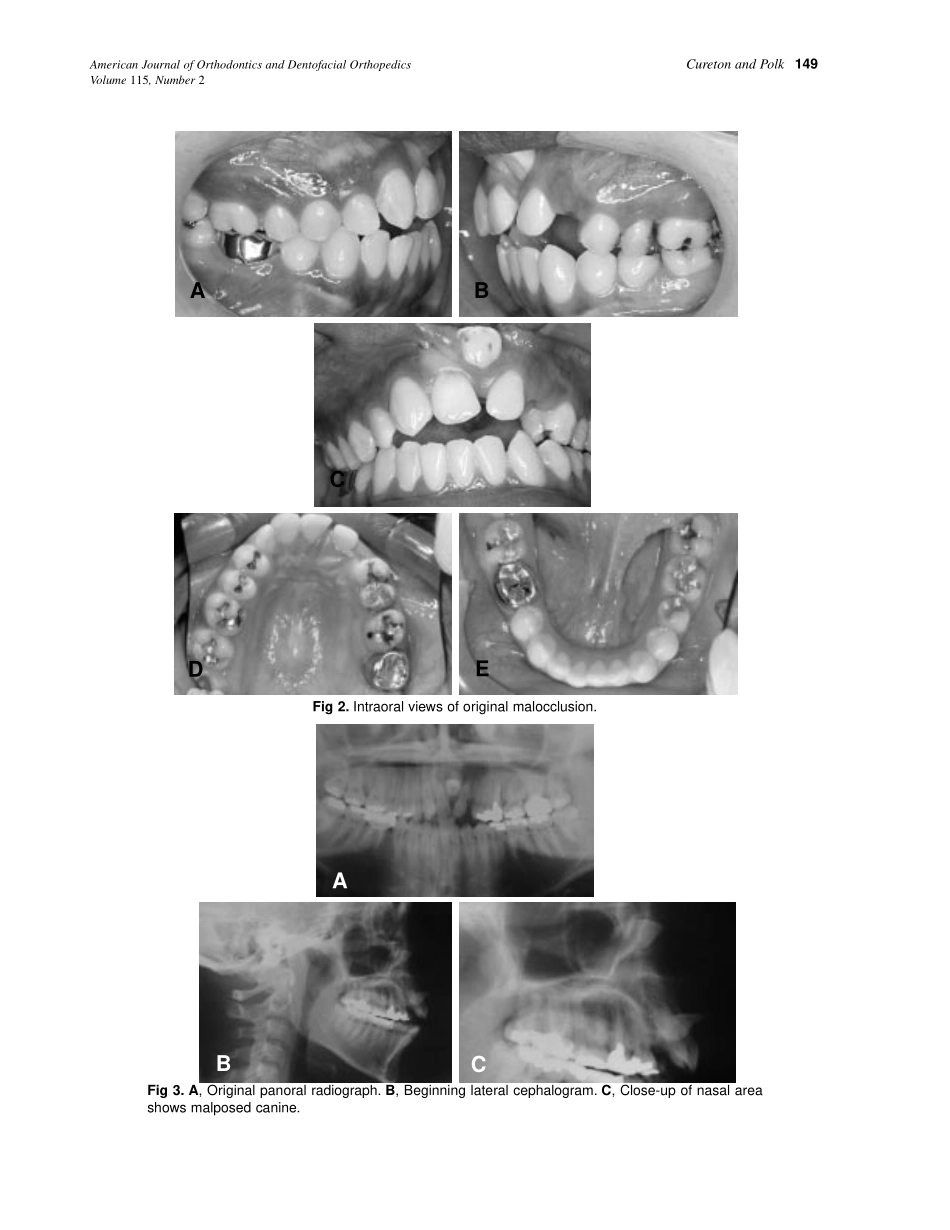

148CASEREPORTApatientwithaskeletalClassIIDivision1maloc-clusionexhibitedatransposition,canineimpaction,severelydilaceratedcentralincisorroot,congenitallymissingmandibularsecondpremolarandananterior...